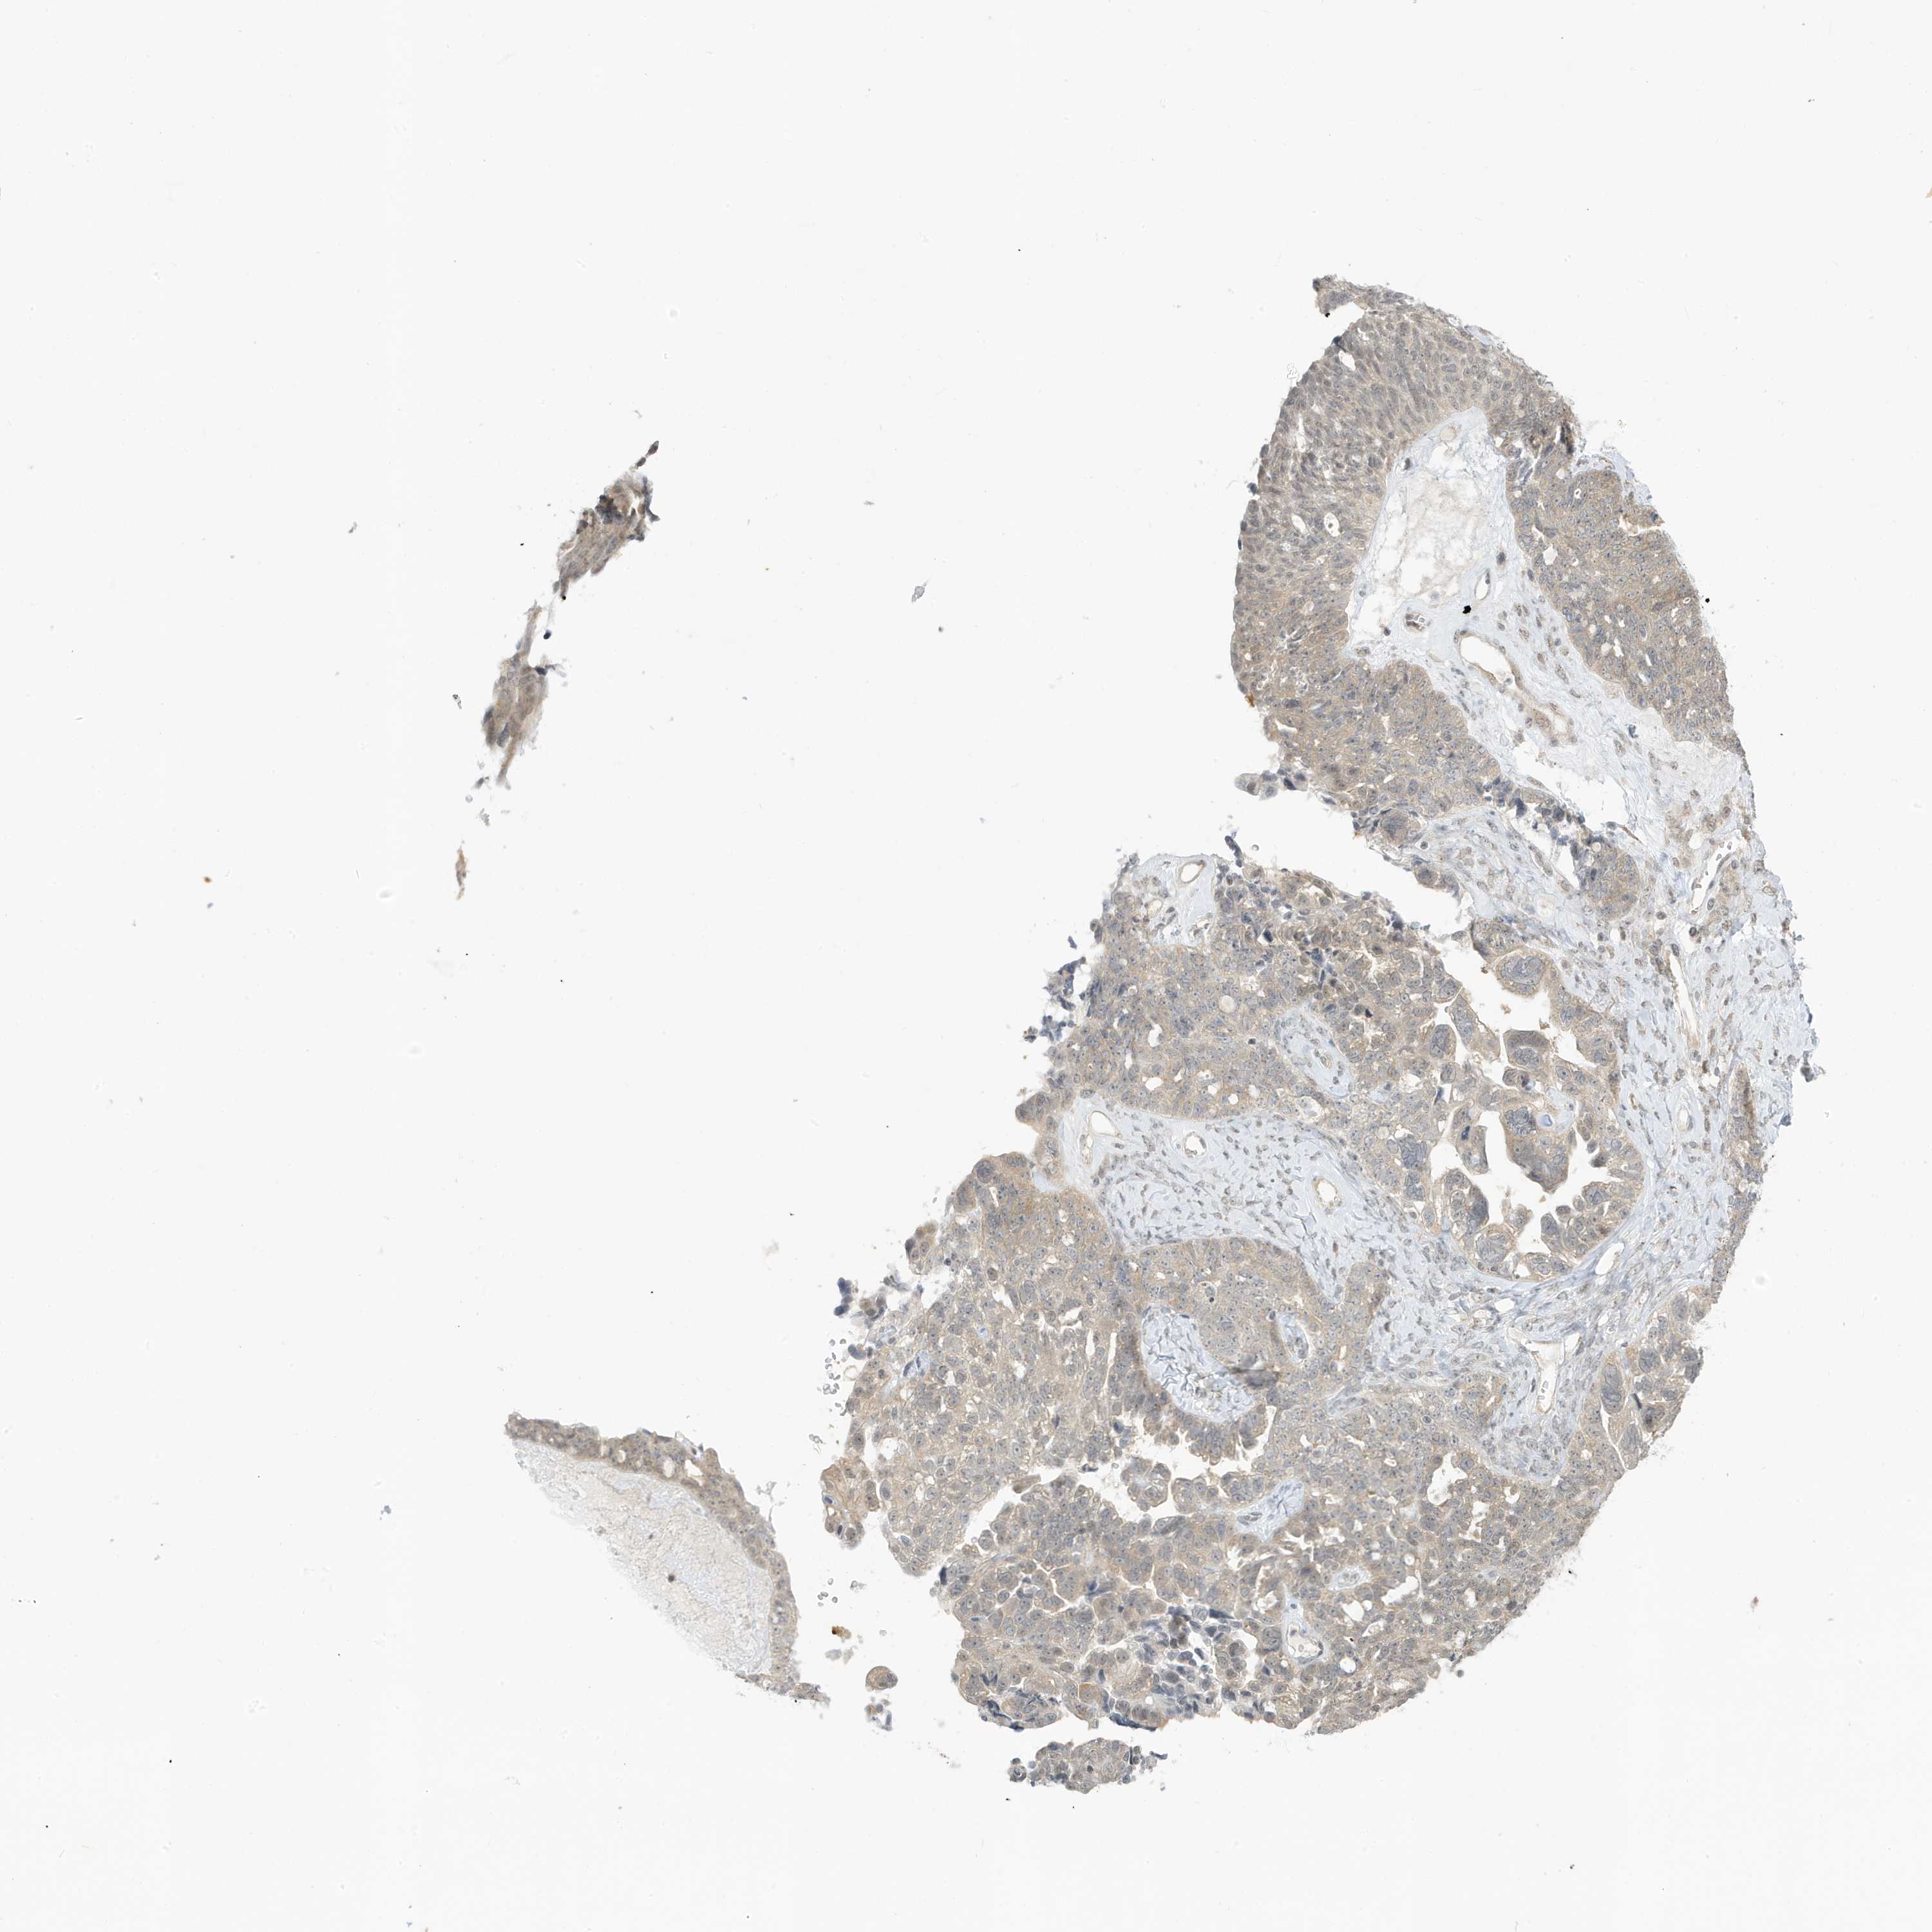

OVARIAN CANCER - Protein expressioni

A mouse-over function shows sample information and annotation data. Click on an image to view it in a full screen mode. Samples can be filtered based on level of antibody staining by selecting one or several of the following categories: high, medium, low and not detected. The assay and annotation is described here.

Note that samples used for immunohistochemistry by the Human Protein Atlas do not correspond to samples in the TCGA dataset.

Antibody stainingi

Antibody staining in the annotated cell types in the current human tissue is reported as not detected, low, medium, or high, based on conventional immunohistochemistry profiling in selected tissues. This score is based on the combination of the staining intensity and fraction of stained cells.

Each image is clickable and will lead to virtual microscopy that enables deeper exploration of all samples and also displays staining intensity scores, fraction scores and subcellular localization as well as patient and tissue information for each sample.

Antibody HPA034980

Antibody HPA034981

Cystadenocarcinoma, mucinous, NOS